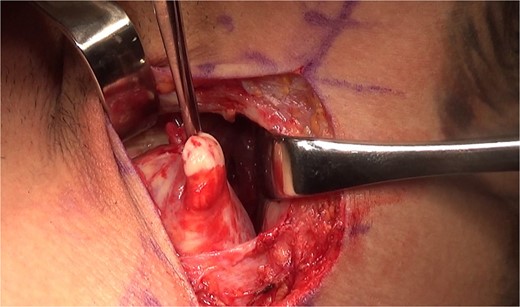

Given the complete rupture on the MRI and the high functional demand of the patient, surgical treatment was indicated and performed 10 days post-injury. The patient was positioned in a right lateral decubitus position with the left upper limb in 90° abduction (Fig. 3). A single 8 cm incision was made at the posterior axillary fold (Fig. 4). After identifying the radial nerve, a complete tear of the teres major at the myotendinous junction was visualized (Fig. 5). The tendon was tied with FiberWire (Arthrex, Naples, FL, USA) (Fig. 6) and its mobility confirmed. The humeral insertion site was exposed, debrided, drilled with two parallel holes 3 cm apart, and fixed with two Pec Buttons. The sutures were tensioned to stabilize the tendons. The shoulder’s range of motion was evaluated, confirming adequate repair tension (Fig. 7), and the incision was sutured. Final intra-op radiographic image is shown in Fig. 8. Post-surgery, no neurovascular changes were noted.

Post-surgery anteroposterior radiographies of the arm showing both Pec Buttons used for the teres major repair.